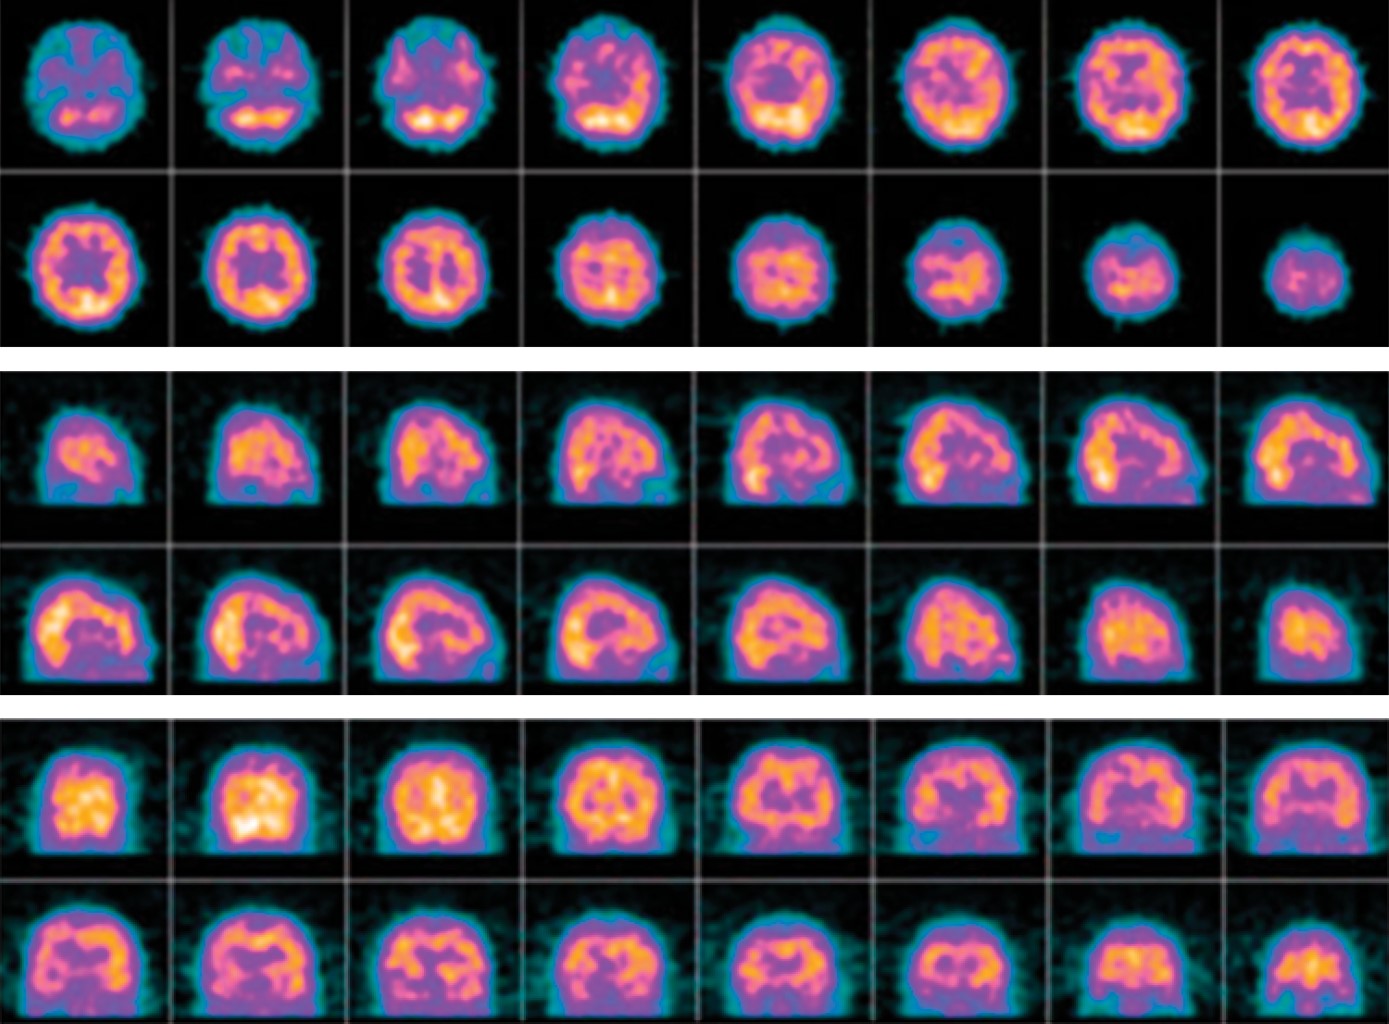

We present the clinical case of a 59-year-old patient with sepsis due to polymicrobial pneumonia with viral isolates conditioning bacterial infection and thrombosis. His chest scannography reported basals collapses with atelectasis and reticular interstitial infiltrates; Evolved with cognitive impairment related to multi-infarction vascular brain disease documented by single-photon emission brain tomography by nuclear medicine due to normal scannographies studies; Given the neurological evolution, extension studies were carried with transthoracic duplex Doppler echocardiogram which was normal, as well as a contrasted study of four neck vessels, electrical rhythm holter and complete metabolic profile also normal. We conducted a review in the literature with a view to providing understanding and evidence of the direct relationship between septic syndromes and viral infections with different states of hypercoagulability, inflammation and apoptosis.

Figure 1